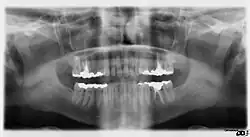

DXIS — отображение в реальном времени- Стрелки указывают на две вертикальные белые линии, которые представляют собой кальцификаты в первой части (проксимальном компоненте) внутренней сонной артерии на панорамных рентгенограммах

- Линия, изображающая панорамную рентгенограмму с овоидной атеромой в области бифуркации общей сонной артерии (CCA), когда она раздваивается (делится) в шее на внутреннюю сонную артерию (ICA), которая снабжает кровью головной мозг, и наружную сонную артерию (ECA), которая снабжает кровью лицо и рот